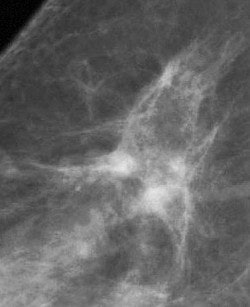

![]() ![]() |

DSPM images acquired on the Mammomat 3000 Nova, including zoom (middle) and spot magnification (below). Images courtesy of Dr. Wolfgang Matzek.